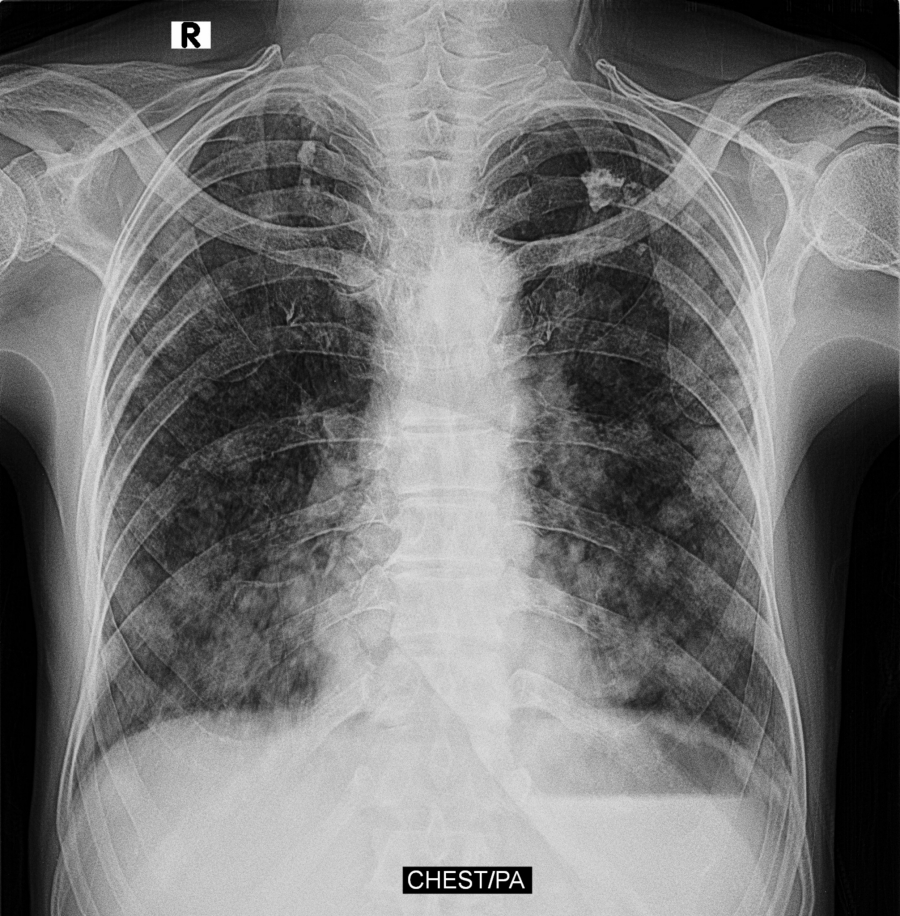

TUBERKULOZA ZARAZNIJA OD KOVIDA I SIDE Doktorka za Alo! otkriva koliko je ova bolest opasna, koliko u Srbiji godišnje ima slučajeva i ko su ugrožene grupe

Iako su lekovi za lečenje tuberkuloze otkriveni još polovinom prošlog veka, danas u svetu od ove bolesti boluje više osoba nego ikada u istoriji čovečanstva. Ipak, u Srbiji je stopa obolevanja veoma niska, a ekipa Alo! istraživala je kako da se zaštitimo od ove zarazne bolesti, koje su rizične grupe koje najčešće pogađa tuberkuloza, ali i koliko traje lečenje.

- Tuberkuloza je zarazna bolest koja se prenosi udisanjem vazduha u kojem se nalaze bacili. Prvi simptomi koje lekari prepoznaju su dugotrajan kašalj, malaksalost, znojenje, temperatura 37,5 - kaže na početku razgovora za Alo! doktorka Ljiljana Timotijević.

- Prošle godine smo u Beogradu dijagnostikovali tuberkulozu kod 120 pacijenata, što je za višemilionski grad veoma dobra statistika. Takođe važno je reći da klinička slika nije onakva kakva je bila pre 30 godina. Danas imamo lekove za uspešnu borbu protiv tuberkuloze, kao i sve uslove za ambulantna i bolnička lečenja - navela je doktorka Timotijević, i objasnila da postoje rizične grupe koje su podložnije ovoj bolesti.